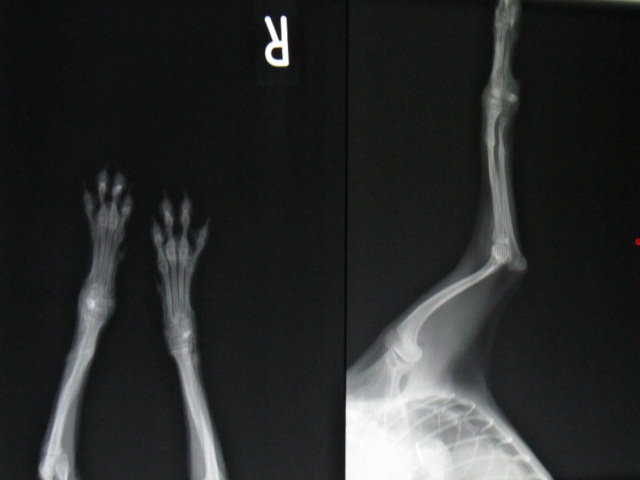

抜ピン後のレントゲンです。

体重が小さいワンちゃんは骨がつきにくいので治療が大変です。

今回は順調に回復してくれました。